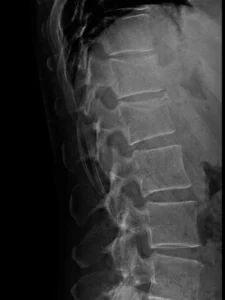

Radiología

Radiografías AP y lateral de columna lumbar, incluye los segmentos dorsales distales. Fractura con reducción de la altura, a predominio anterior, de los cuerpos de D12 y L1, mejor visualizada en la proyección lateral. Irregularidad del ángulo anterosuperior en ambos niveles y probable protrusión del muro posterior de L1 hacia el canal.

Hallazgos principales en Rx:

- En la proyección lateral se identifica pérdida de altura del cuerpo vertebral de D12 y L1, predominante anterior, compatible con fractura por compresión.

- Puede determinar discreta cifosis segmentaria en la unión toracolumbar.

- Alteración del muro posterior o trazo vertical sugerente de fractura más compleja (dato que suele requerir TC).

Comentario didáctico: La Rx puede detectar la fractura y orientar el nivel, pero subestima con frecuencia el compromiso del muro posterior, el canal y los elementos posteriores.